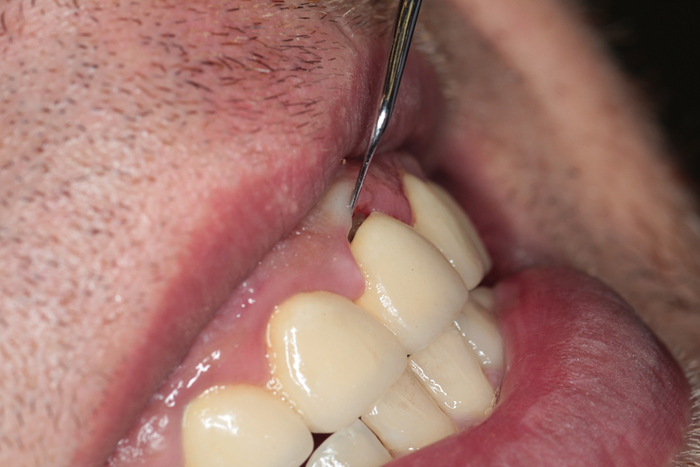

Вживую это выглядит вот так.